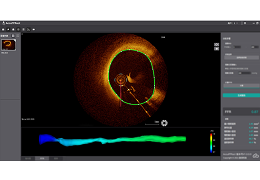

成像智能。

Eclipse 成像智能功能提供强大的处理能力和最佳质量的影像,同时减少质量错误并提高剂量效率。

凭借 AI、专有算法和先进的影像处理能力,提供出色的影像质量和无与伦比的诊断信心。